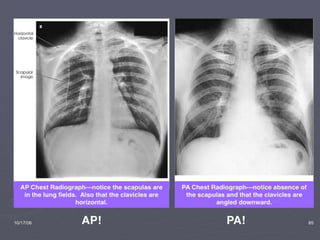

PA Film

Trachea and Mediastinum